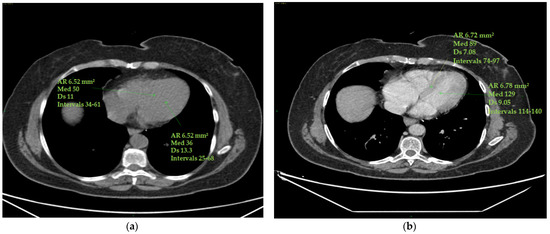

The epicardial adipose tissue (EAT) density was assessed using a specialized workstation (GE Healthcare, General Electric, Boston, MA, USA) at baseline and at the end of therapy. EAT density was measured on basal scans in a 4-chamber projection, at the level of the anterior interventricular sulcus, at the origin of the posterior interventricular artery within the posterior interventricular sulcus and at the level of the cardiac apex (Figure 2).

Figure 2. (ac) Epicardial fat density measurement. Using a 4-chamber projection, epicardial fat density was assessed on axial perspective basal CT scans, using a manually placed ROI (with a mean area of 6 mm2) within the anterior interventricular sulcus (a), posterior interventricular sulcus (origin of the posterior interventricular artery) (b) and cardiac apex (c). The figure shows an example of the area of the region of interest (Ar ROI), the mean (med), the standard deviation (Ds) and the range (intervals) of hounsfield units measured.